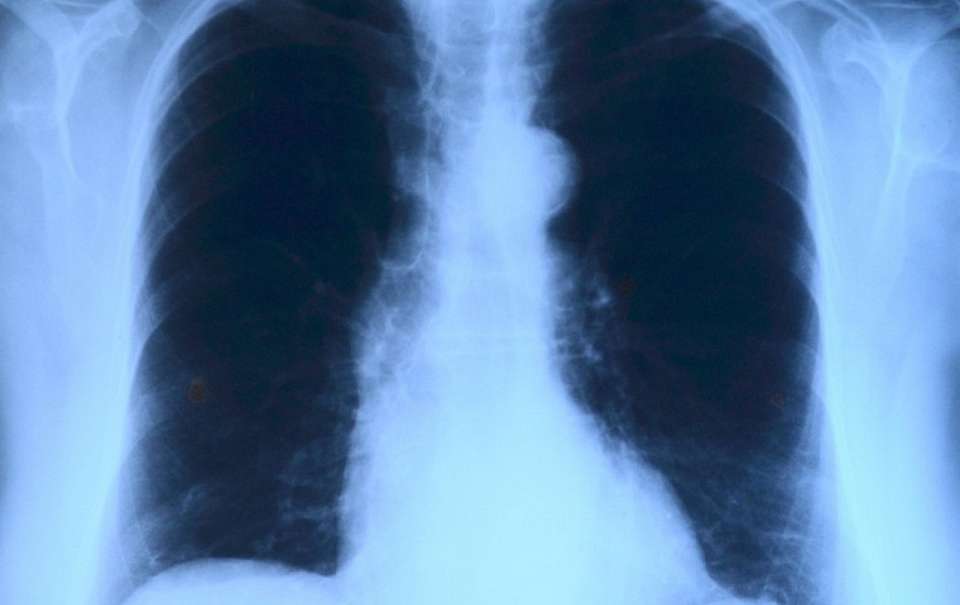

Там уточнили, что с начала текущего года эта болезнь была выявлена у одного ребенка и трех взрослых жителей района. Причем два человека из последней категории не проходили флюорографию более трех лет.

В районе выявлен также случай рецидива туберкулеза с заразной формой.

Местные власти назвали ситуацию в районе крайне неблагоприятной, поскольку туберкулез признан очень опасным социально-значимым заболеванием. И призвали жителей как можно скорее пройти флюорографию.